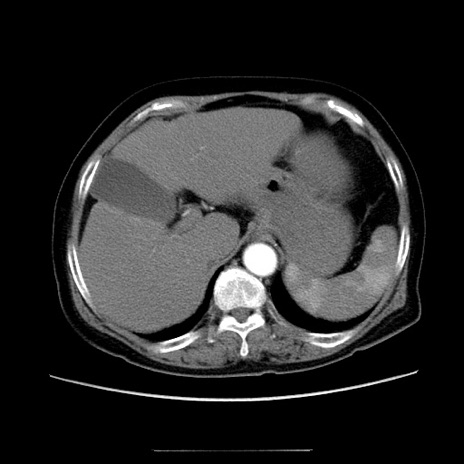

冠状断像

【症例】70歳代女性

【主訴】お腹が張る

【現病歴】1週間くらい前から腹部膨満の自覚あり。昨日夜から増悪したため、本日救急外来受診。

【身体所見】意識清明、BT 36.5℃、BP 165/106mmHg、HR 80bpm、SpO2 98%、腹部:膨満、軟、自発痛・圧痛なし、触診にて不快感あり、腸蠕動音:減弱

【データ】WBC 12600、CRP 1.04